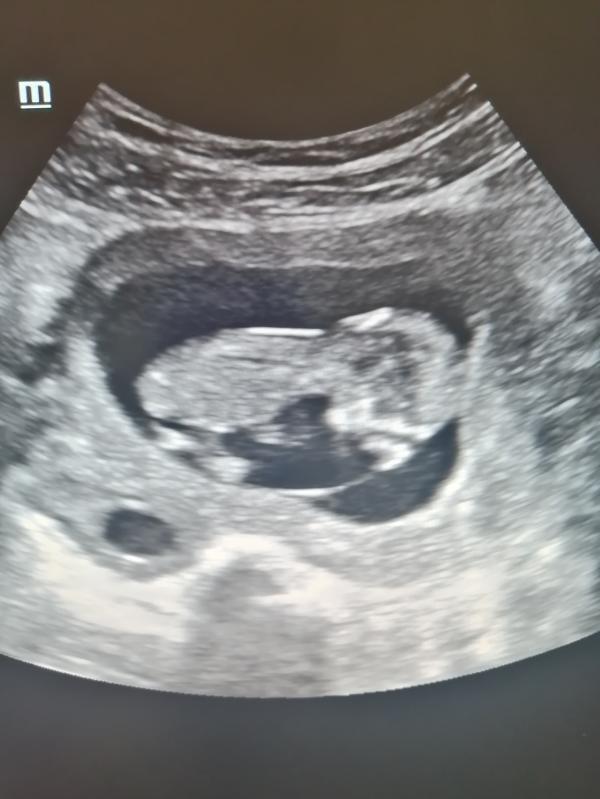

Наш первый скрининг 😍

Интересно, у меня будет девочка или мальчик🥰

А Вы кого ждёте?)

#первыйскрининг #нашмалыш